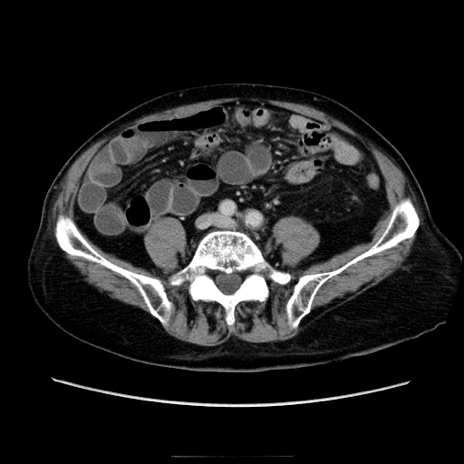

冠状断像

症例21(横断像)

【症例】70歳代男性

【現病歴】肝硬変・肝細胞癌にてかかりつけの方。約9時間前に食後より腹痛出現。症状が徐々に増悪し、嘔吐出現したため来院。

【既往歴】肝硬変、肝細胞癌(RFA、TACE後)